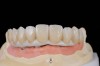

Fig 8. The full-arch titanium framework, which will receive individual lithium-disilicate crowns.

Figure 8